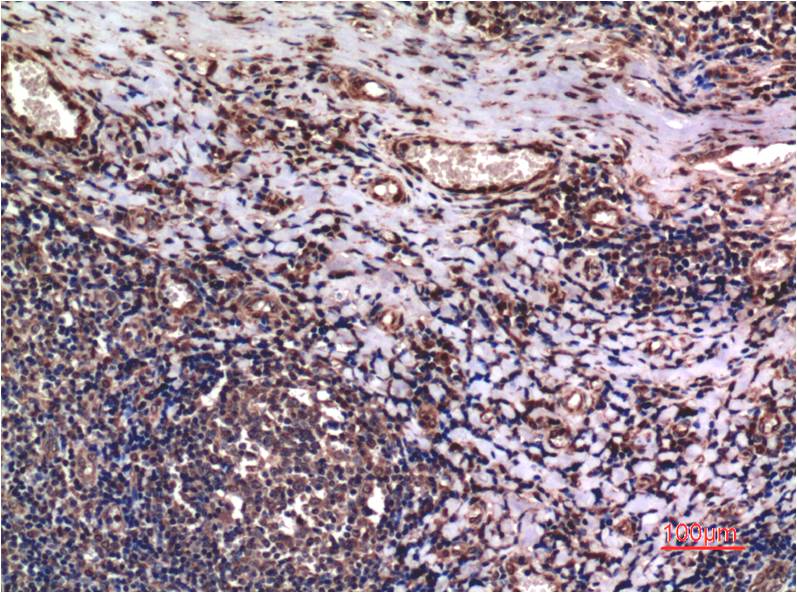

Immunohistochemistry analysis of paraffin-embedded Human Lung Carcinoma Tissue using Cyclin B1 antibody.High-pressure and temperature Sodium Citrate pH 6.0 was used for antigen retrieval. |